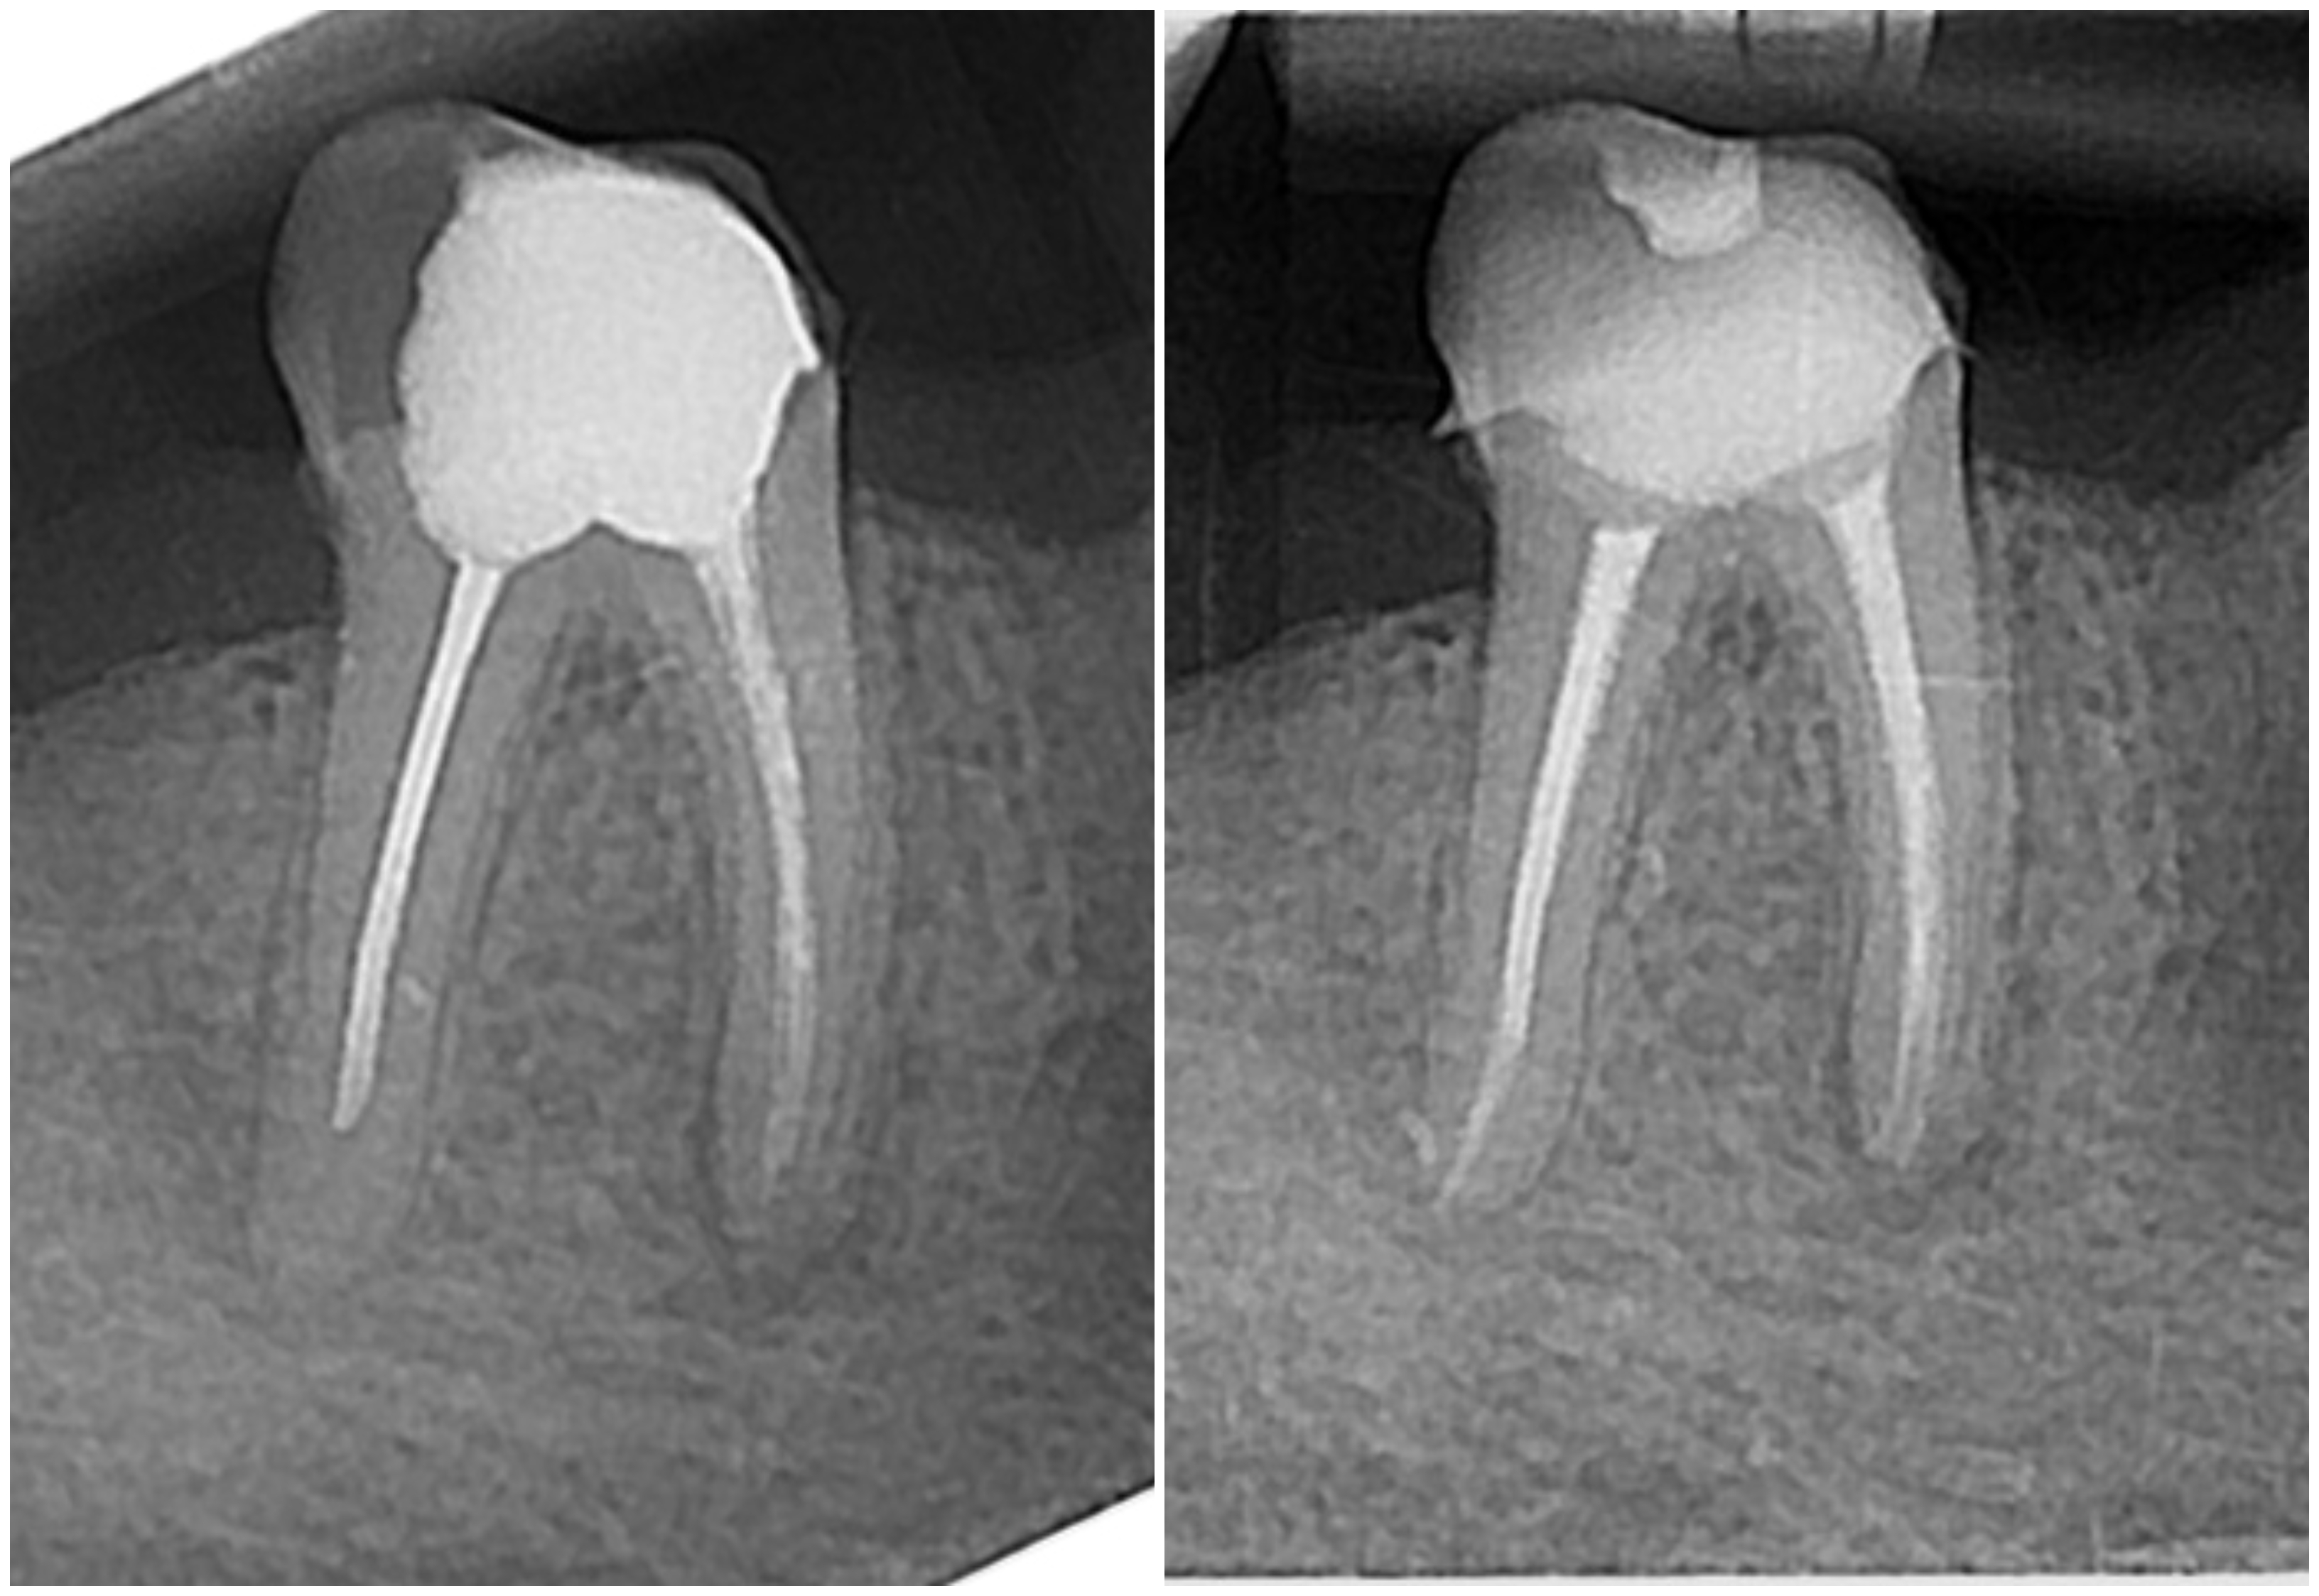

Endodontska terapija provodi se kada karijes uništi zub (caklinu i dentin) te dođe do živca (pulpe).

Ako se zub s upalnim procesom ne liječi, dolazi do širenja upale na kost i stvaranja upalnog procesa oko vrha korijena, odnosno dolazi do razvoja granuloma.

Endodontska terapija započinje uklanjanjem karijesom zahvaćenog zubnog tkiva, nakon čega se odstranjuje upaljena zubna pulpa te se kemijski i mehanički čisti zubni kanal radi uklanjanja bakterija i inficiranog dentina.

Tretirani zub jednako je funkcionalan kao i vitalni zubi, a sam korijen se može koristiti za protetske nadomjestke (krunice i mostove).